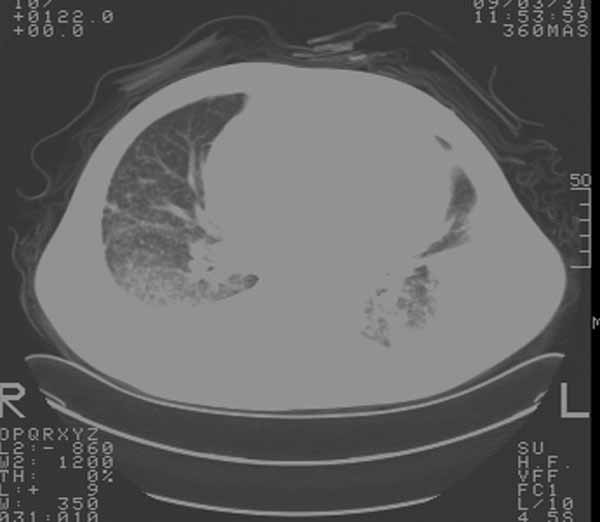

以下是引用余辉在2009-3-31 18:43:00的发言:[br]肺水肿,双侧心腔积液,心包积液,心影增大,疑似心衰

以下是引用wangyong1977在2009-3-31 20:46:00的发言:[br]肺水肿,双侧胸腔积液,心包积液,心影增大,疑似心衰 [br]

以下是引用宇宙ct在2009-3-31 18:57:00的发言:[br]肺水肿,双侧心腔积液,心包积液,心影增大,疑似心衰 [br] [br]